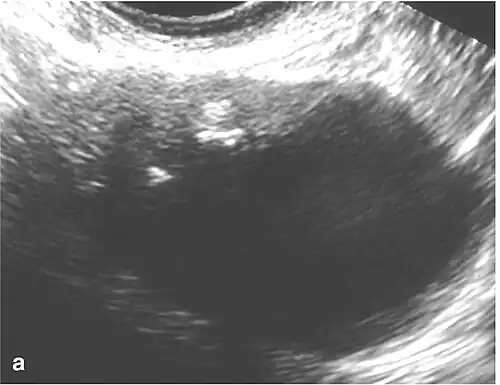

The difficulty in screening for SCC revolves around the creation of effective strategies with a positive predictive value. The timing aspect is crucial due to the lack of a specific timeframe for the onset of invasive disease or the interval stage between stage I and stage III carcinomas.[17] Ultrasound screening provides a detailed view of the ovaries, identifying morphologic changes as potential signs of malignancy. Key diagnostic factors include the presence of abnormalities, ovarian size, blood flow, and abdominal/pelvic fluid. The persistence of abnormalities after four to six weeks may decrease the occurrence of false positives. Screening protocols, often based on morphologic indices, utilize transvaginal ultrasound findings like cyst wall structure, septation, papillary projections, echogenicity, and ovarian volume to effectively detect malignancy.[17]